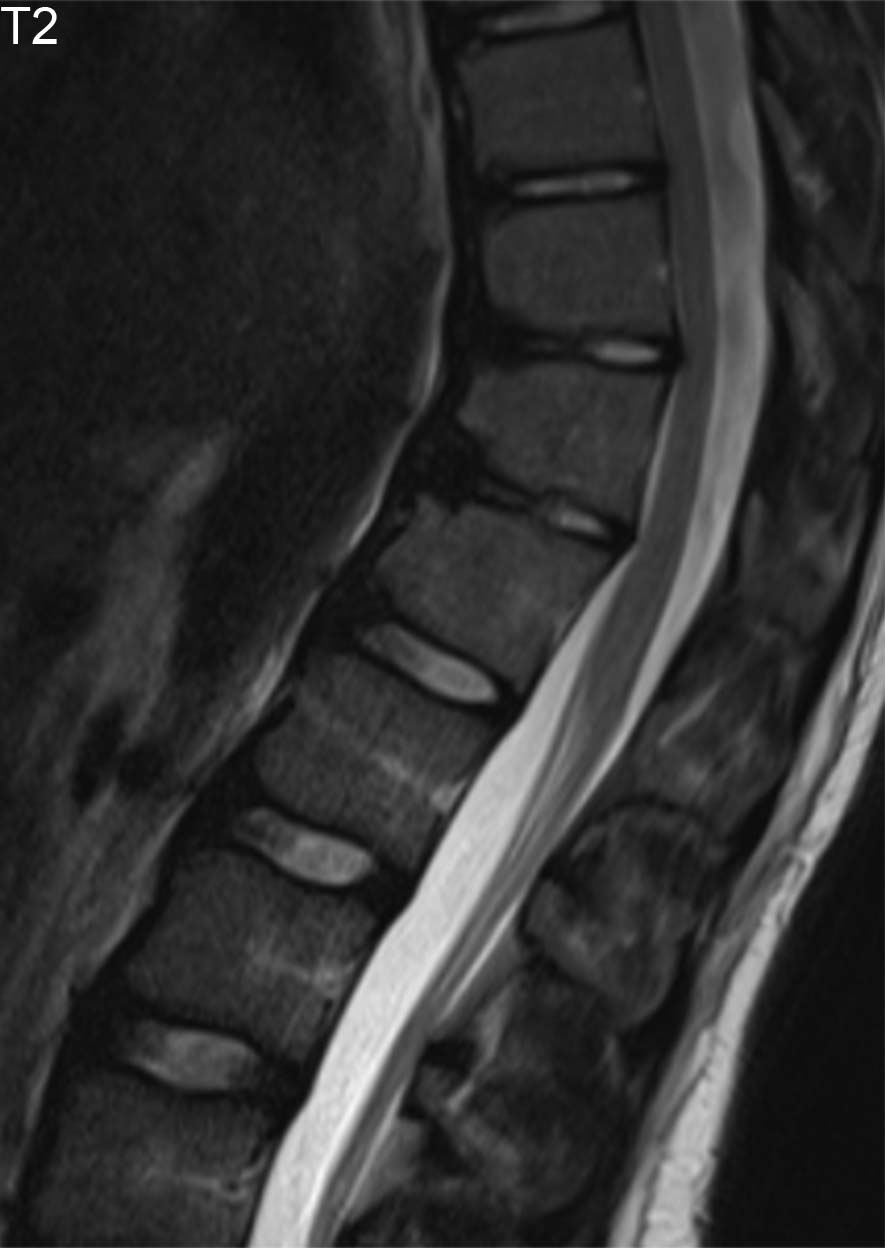

- Resonancia magnética: si en las pruebas anteriores observamos alguna lesión sospechosa de ser tumoral o infecciosa, pasaremos a realizar esta prueba. Con ella obtendremos imágenes detalladas de las estructuras óseas y tejidos blandos del organismo del paciente.